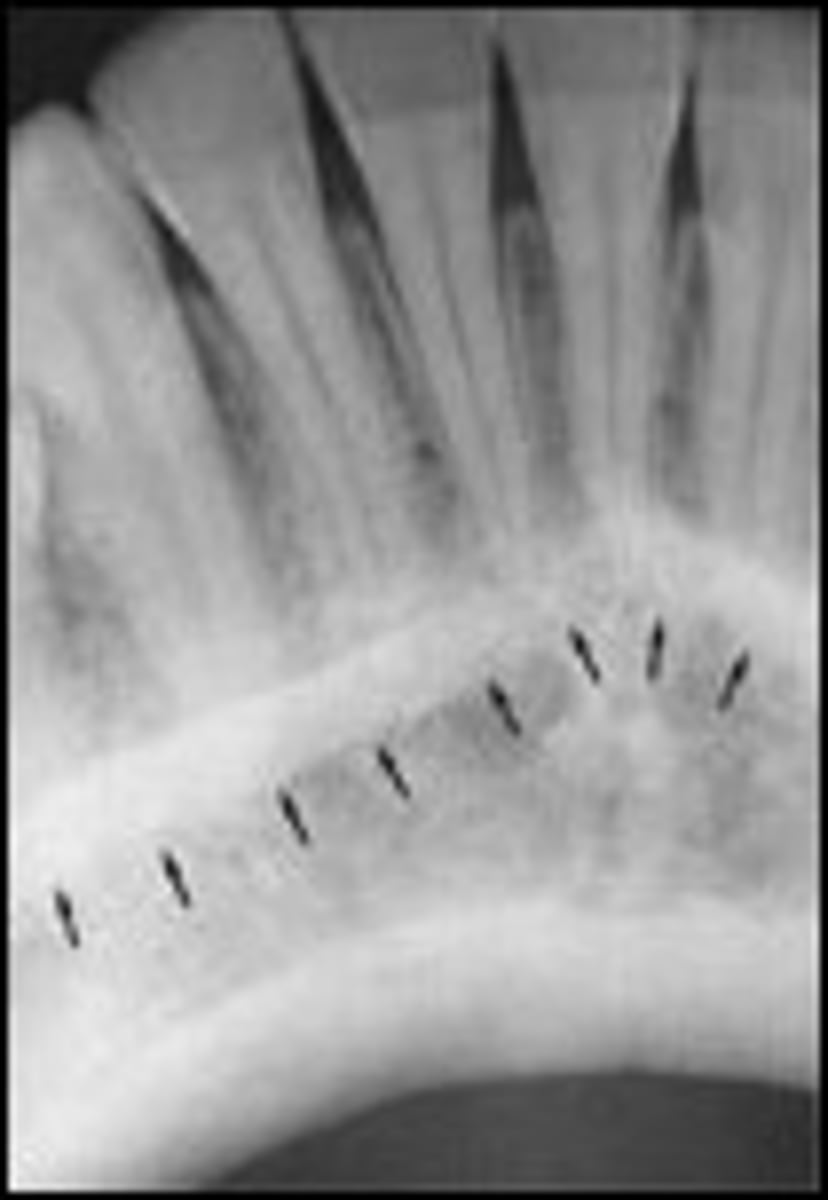

Facial erosion due to acidic beverages

Amelogenesis Imperfecta (xray)